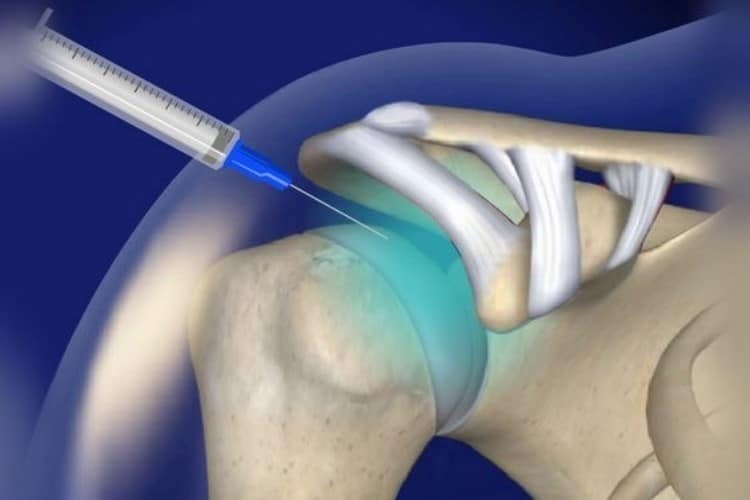

تزریق پی آر پی:

از خون خود بیمار تهیه میشود. با جداسازی پلاکتها و تزریق آن به مفصل آسیبدیده، فاکتورهای رشد طبیعی آزاد میشوند که به ترمیم بافتها، کاهش التهاب و تحریک بازسازی غضروف کمک میکنند. پی آر پی مفصلی بیشتر برای ترمیم و بازسازی مفصل و کاهش تدریجی درد کاربرد دارد.

- PRP بیشتر نقش ترمیم و بازسازی بافت آسیبدیده را ایفا میکند.

«تزریق پیآرپی زانو یک روش غیرتهاجمی و بدون نیاز به انجام جراحی بوده که میتواند درد و سایر علائم ناشی از مشکلات مفصلی و اسکلتی را بهبود ببخشد.»

- دکتر عباس بهراد، متخصص ارتوپدی، در وبسایت خود بیان میکند:

«پیآرپی یا پلاسمای غنی از پلاکت روشی برای کاهش درد و درمان آرتروز درجه ۲ و ۳ زانو محسوب میشود. در این روش از خاصیت ترمیمکنندگی و محرک رشد پلاکتها، به ترمیم بافتهای آسیبدیده کمک میشود.»

- دکتر مجید قربانزاده، متخصص ارتوپدی، در وبسایت خود مینویسد:

«تزریق پیآرپی آسیب مفصلی را ترمیم میکند و از پیشرفت آرتروز زانو جلوگیری میکند. کاهش التهاب و فرایند ترمیمی سریع، ایمن و اثربخش را برمیانگیزد»